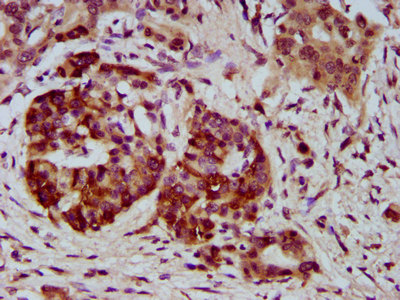

IHC image of CSB-PA848831LA01HU diluted at 1:400 and staining in paraffin-embedded human pancreatic cancer performed on a Leica BondTM system. After dewaxing and hydration, antigen retrieval was mediated by high pressure in a citrate buffer (pH 6.0). Section was blocked with 10% normal goat serum 30min at RT. Then primary antibody (1% BSA) was incubated at 4°C overnight. The primary is detected by a biotinylated secondary antibody and visualized using an HRP conjugated SP system.